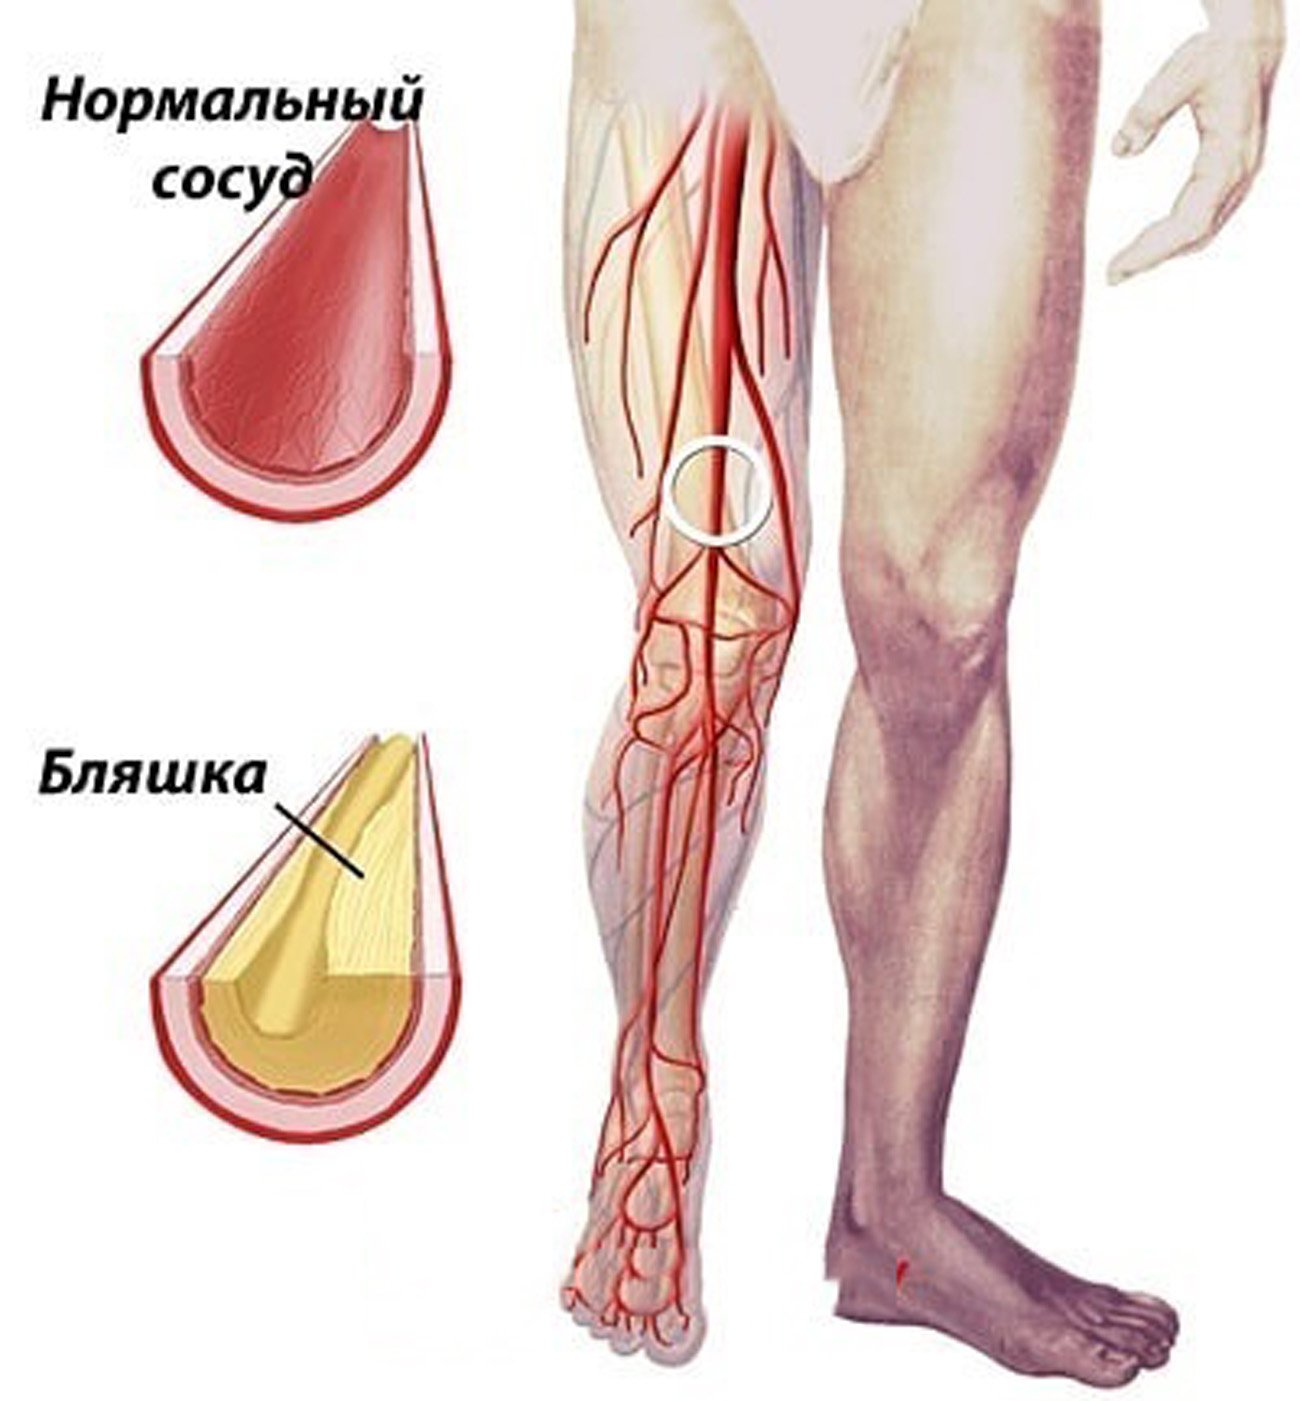

Изображения, связанные с атеросклерозом нижних конечностей и его лечением